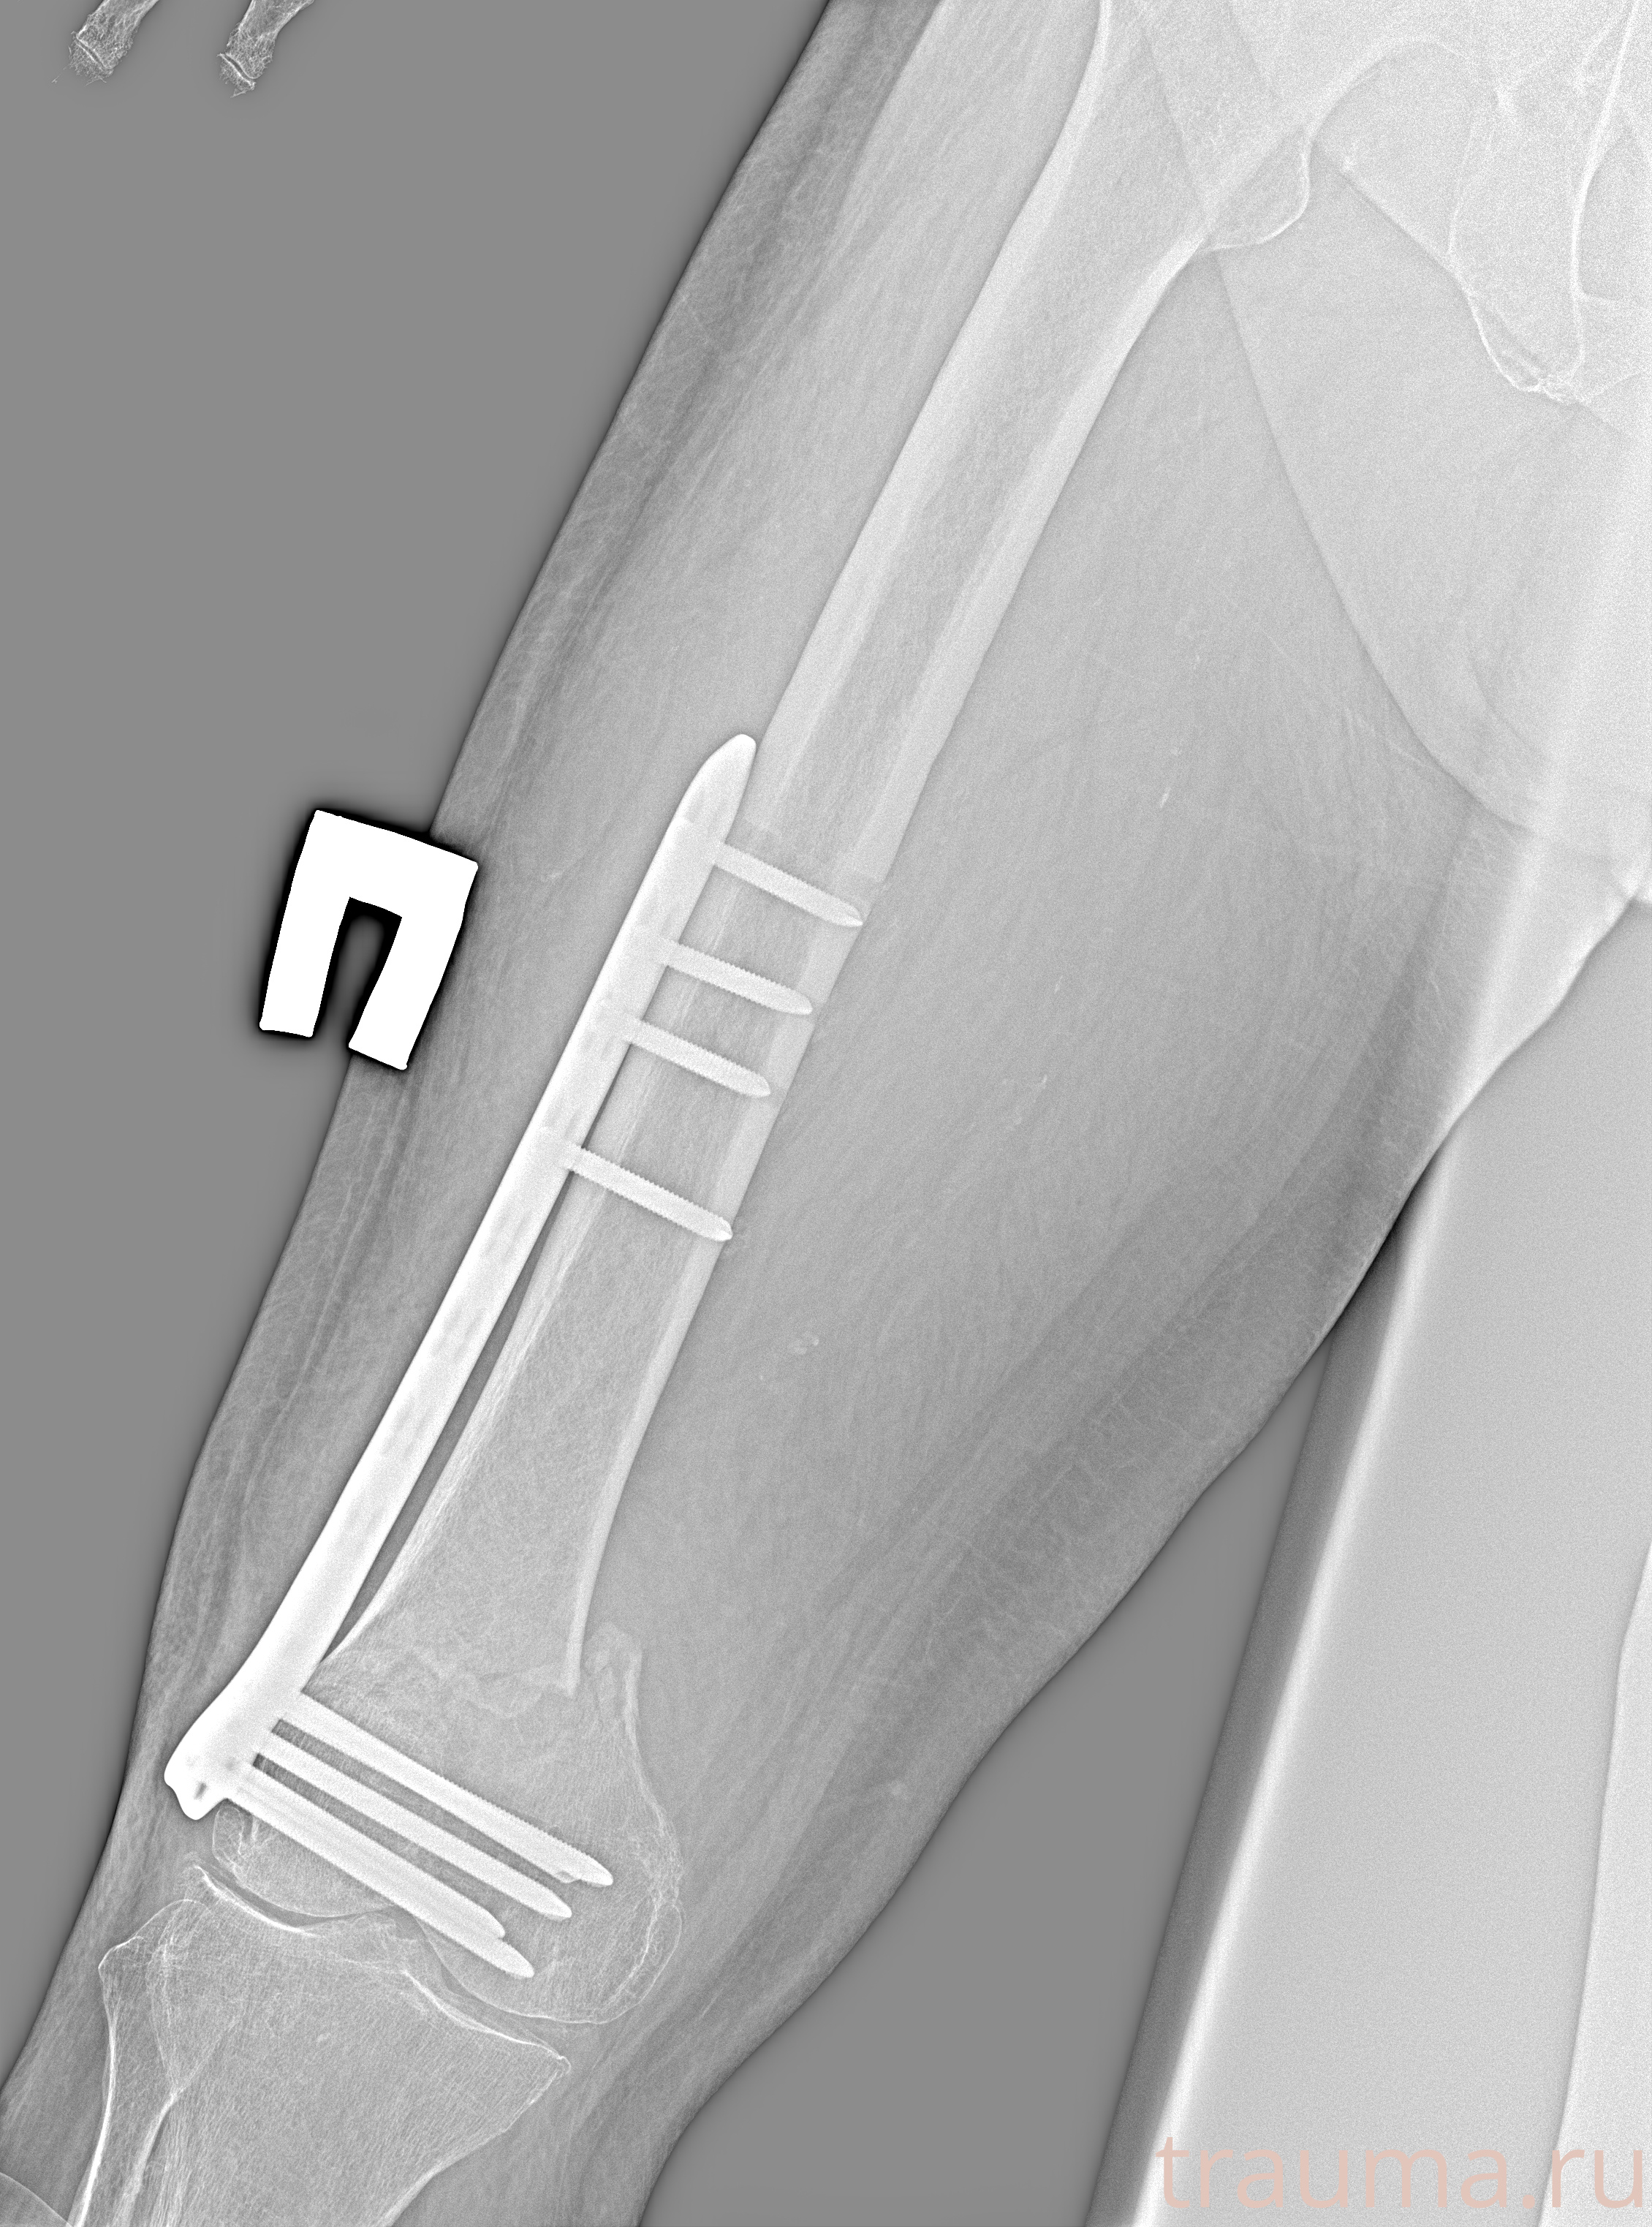

Рентгенограммы

Рентген на дому: по вашему адресу приезжает врач-рентгенолог, травматолог-ортопед с мобильным рентгеновским аппаратом, проводит диагностику травмы или заболевания, делает необходимые рентгенограммы, дает рекомендации по дальнейшему лечению. Получить качественные снимки в домашних условиях возможно благодаря уникальной методике, разработанной МосРентген Центром для института  Склифосовского